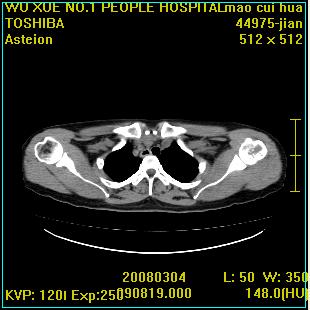

标题: CT12025:男,50岁,左肩活动受限半年。 [打印本页]

标题: CT12025:男,50岁,左肩活动受限半年。

肩关节骨质破坏呈小囊状,其周软组织轻度肿胀,余未见异常。

考虑:肩袖损伤。建议mri。

左侧肱骨头密度不均匀,高低混杂,周围软组织略肿胀,考虑结核性病变。

考虑左侧肱骨慢性骨髓炎。

左侧肱骨头密度不均匀,高低混杂,髓腔密度稍高,周围软组织略肿胀,肌间隙模糊,考虑慢性骨髓炎可能。密切结合临床!